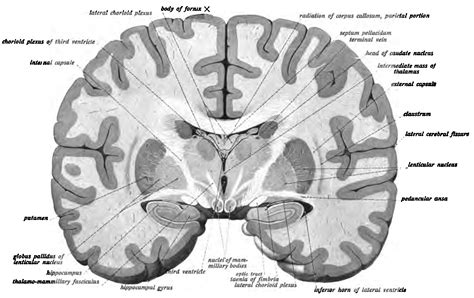

The Basal Nucleus of Meynert is situated in the basal forebrain, a region that includes several nuclei involved in various cognitive and behavioral processes. The BNM is composed of cholinergic neurons, which means they produce and release acetylcholine. This neurotransmitter is crucial for several brain functions, including:

The BNM projects to various brain regions, including the cerebral cortex, hippocampus, and amygdala, influencing their activities and contributing to higher-order cognitive functions. The cholinergic neurons of the BNM are particularly important for modulating the activity of these target regions, ensuring optimal cognitive performance.